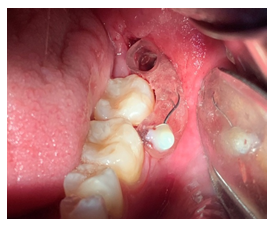

Se realizó en un segundo tiempo quirúrgico la enucleación de la membrana quística completa de la cavidad. Se presentó la biopsia excisional, se aplicó solución carnoy en la cavidad durante 3 minutos para la eliminación de células epiteliales residuales del queratoquiste odontogénico.

Figura 14 (A) Enucleación de la membrana quística, (B) Se presenta la cavidad con la eliminación total de la membrana, (C) Biopsia Excisional, (D) Aplicación de solución carnoy. Fuente: Historia Clínica. Especialización Cirugía Bucal ULAC-IDOLA. 2022